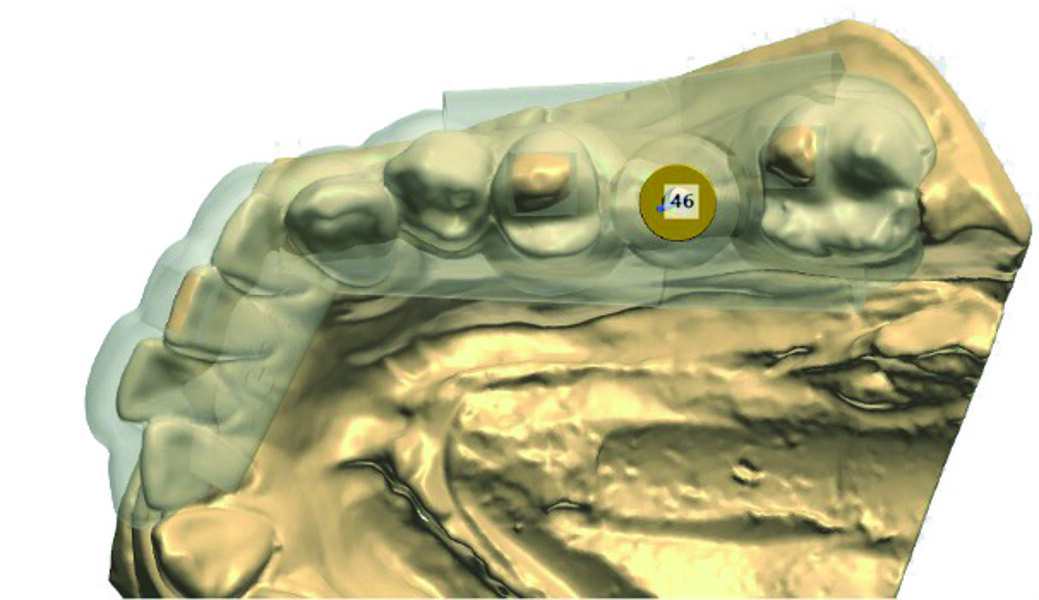

L’empreinte dentaire en silicone a été coulée puis le modèle en plâtre numérisé avec un scanner de table. Cette étape peut aussi être réalisée à l’aide d’une caméra optique (Fig. 3).

Grâce au logiciel d’implantologie Implant Studio de 3shape, nous avons pu visualiser la largeur et la hauteur de la crête édentée, afin d’étudier la faisabilité du projet prothétique.

Fig. 3 : Image du scannage des empreintes au plâtre.

Fig. 4 : Planification implantaire.